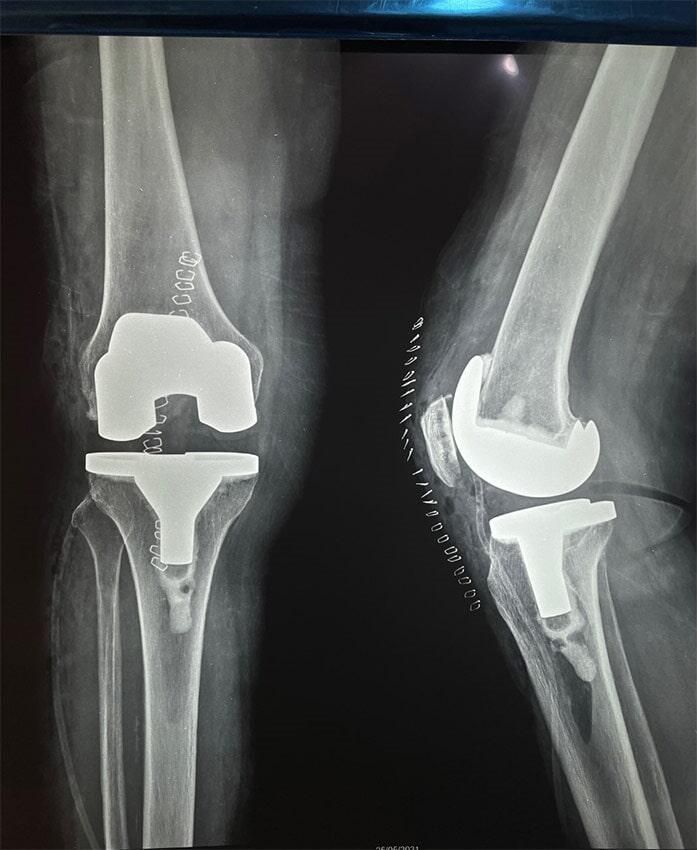

ButtonARTROUPN - Reemplazo de rodilla